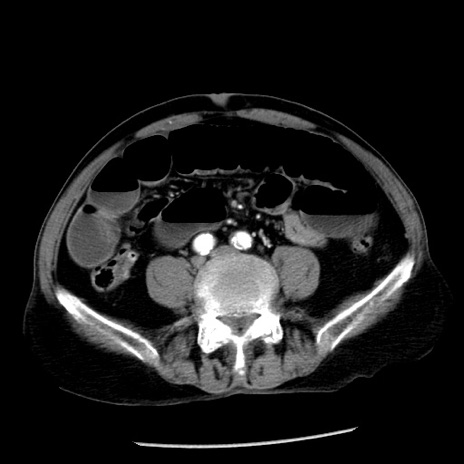

症例26(横断像)

冠状断像

【症例】80歳代男性

【主訴】嘔吐

【現病歴】昨晩2回嘔吐あり、今朝になっても嘔吐あり。来院。

【既往歴】胃潰瘍

【身体所見】意識清明、BT 37.6℃、BP 166/95mmHg、HR 100bpm、SpO2 97%、腹部:平坦・軟、腸蠕動音聴取良好、圧痛なし。

【データ】WBC 21900、CRP 1.46